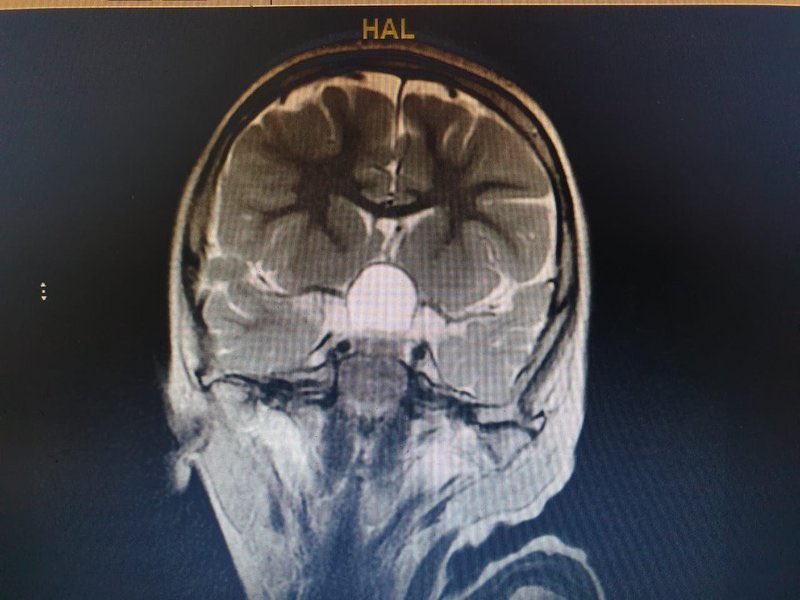

عملية هي الأولى من نوعها بالمجمع واستمرت 7 ساعات إزالة ورم بِقَاعِ الجمجمة يُعيد "الإبصار" لطفل بمجمع الملك فيصل بـ #الطائف

عملية هي الأولى من نوعها بالمجمع واستمرت 7 ساعات

إزالة ورم بِقَاعِ الجمجمة يُعيد "الإبصار" لطفل بمجمع الملك فيصل بـ #الطائف